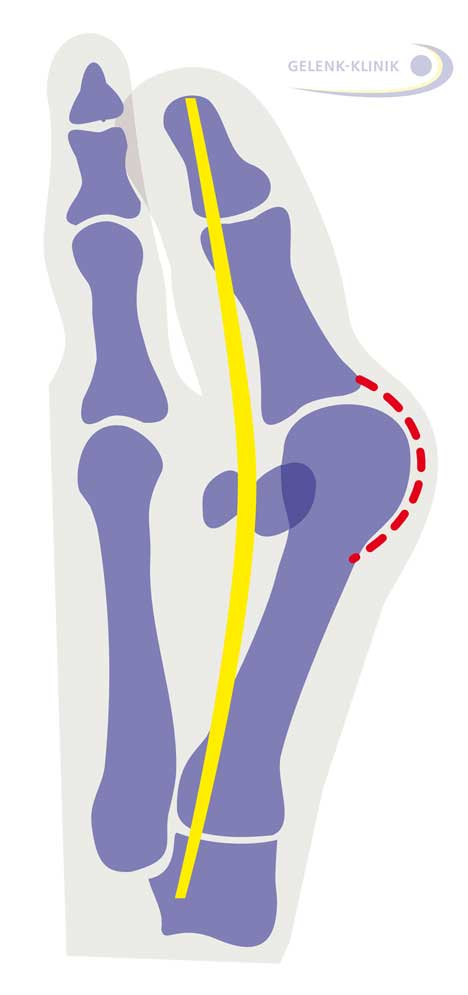

Dabei neigt sich der große Zeh in Richtung Fußaußenrand. Am Großzehengrundgelenk (Metatarsophalangealgelenk) tritt beim Hallux valgus das oft schmerzhaft entzündete und geschwollene Mittelfußköpfchen hervor und drückt gegen den Schuh. Die Großzehensehne verläuft beim Hallux valgus ebenfalls nicht mehr gerade durch das Großzehengrundgelenk. In Deutschland leiden 23 % der 18- bis 65-Jährigen und mehr als 35 % der über 65-Jährigen unter einem Hallux valgus.

Durch den Zug der Sehnen dreht sich der Großzeh bei einem Hallux valgus aus dem Großzehengrundgelenk heraus – ähnlich wie ein gespannter Bogen. Er neigt sich nach außen, in Richtung der anderen Zehen. Der einwärts gedrehte Großzeh verdrängt die Zehen, wodurch diese ebenfalls eine Fehlstellung annehmen. Ein Hallux valgus tritt daher oft in Verbindung mit Hammerzehen oder Krallenzehen auf.

Beim Hallux valgus sind diese Sesambeine nach außen verschoben. Es entsteht ein Winkel zwischen dem Verlauf des Großzehenstrahls und der Sehne des Zehenbeugers. Je größer dieser Winkel ist, desto ausgeprägter ist die Hallux valgus-Fehlstellung.

Röntgen zeigt das Ausmaß des Hallux valgus

Zusätzliche Informationen über das Stadium des Hallux valgus gibt ein Röntgenbild des Fußes. Dabei misst der Arzt im Stehen – also unter Belastung – die exakte geometrische Abweichung der Fehlstellung von der Normalstellung. Diese Abweichung bezeichnet der Mediziner als Hallux valgus-Winkel. Die Kernspintomographie (MRT) kann Knorpelschäden, Weichteileinklemmungen und Knochenschäden feststellen.

Stadien des Hallux valgus

- Eine Großzehenstellung mit einem Winkel von bis zu 10° gilt als normal.

- Eine milde Hallux valgus-Fehlstellung liegt zwischen 16° und 20° vor.

- Eine mittlere Hallux valgus-Fehlstellung weicht zwischen 21° und 40° ab.

- Eine schwere Hallux valgus-Fehlstellung weicht über 40° ab.

Weichteileingriffe: Behandlung von Sehnen und Gelenkkapsel an der Großzehe

Die Kapsel um das Großzehengrundgelenk hat sich durch die Fehlstellung bereits so verengt, dass die Fehlstellung kontrakt, also nicht mehr aktiv durch den Patienten zurückführbar ist. Auf der Seite des Knicks im Großzehengrundgelenk (rot) ist die Kapsel überdehnt, auf der Gegenseite ist sie verkürzt. Um die Großzehe dauerhaft zu begradigen, löst und erweitert der Fußspezialist die Gelenkkapsel und passt die Länge der Sehnen an, die die Großzehe steuern.